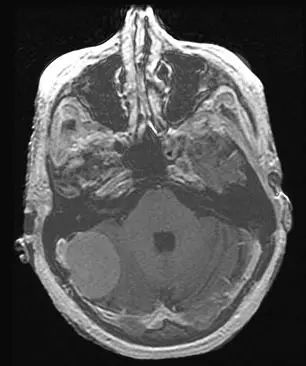

桥小脑角区脑膜瘤占全部脑膜瘤的5%~10%。这些病变需与前庭神经鞘瘤和转移瘤区别开来;影像学特点有助于鉴别诊断。下图为增强MRI扫描T1加权像,显示了经典的前庭神经鞘瘤,表现为“冰淇淋”征,呈圆柱形状,延伸至内耳道(橙色箭头)。神经鞘瘤缺乏脑膜瘤附近常见的硬脑膜增厚。脑干(绿色箭头)被肿瘤所扭曲,导致四脑室(蓝色箭头)受压,造成患者脑积水。此人表现为严重的共济失调与脑干和小脑功能障碍。